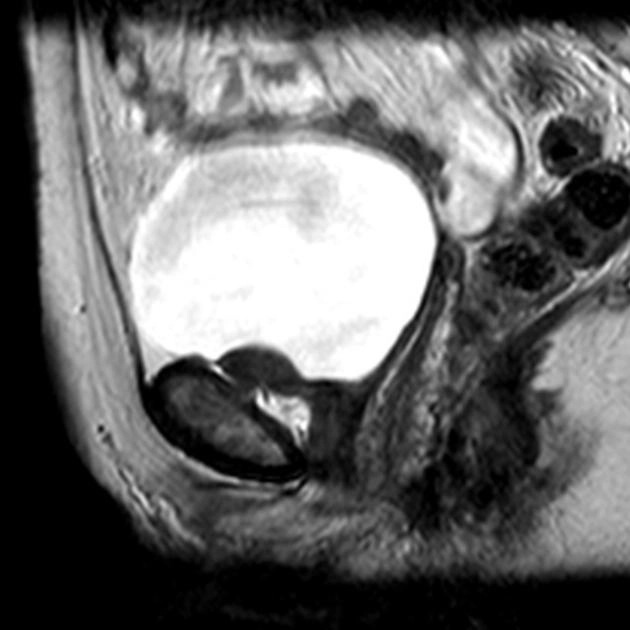

• Khối u bàng quang

U cơ trơn bàng quang (Leiomyoma of the urinary bladder)

Ung thư biểu mô tế bào chuyển tiếp ở bàng quang (Transitional cell carcinoma (urinary bladder))

Phân loại giai đoạn ung thư của bàng quang (Transitional cell carcinoma of the bladder (staging))

Ung thư biểu mô tuyến của bàng quang (Adenocarcinoma urinary bladder)